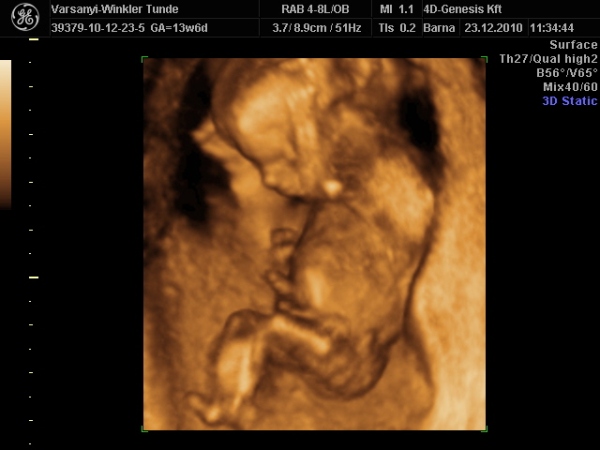

Bár tegnap a dokor bácsi azt mondta, hogy azért lassan vissza kellene vennem a lendületből, mert nem lesz jó vége. Manócska jól van, de tegnap nem tudtuk megnézni. Hasi uh-val próbálkozott, de pont úgy fordult, hogy csak a nagy kobakját láttuk

Gondolta, ha arra van a feje, akkor lentről lehet látni valamit a neméből.